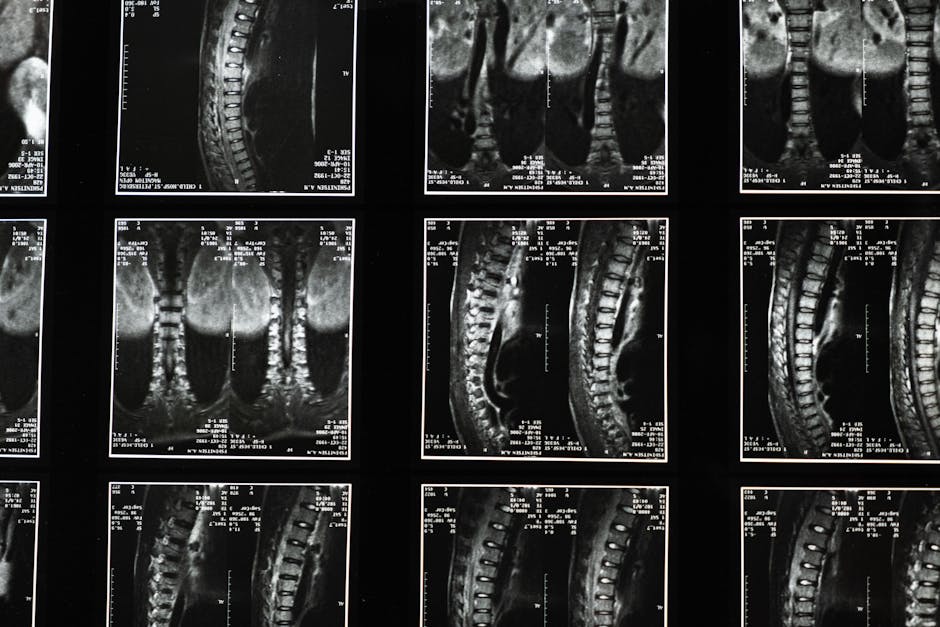

Your spine is the central support structure of your body and houses the nervous system that controls every function. When vertebrae become misaligned, it can cause pain, restricted movement, and interfere with your body's ability to heal itself.

Our spinal alignment care uses precise chiropractic techniques to gently restore proper vertebral positioning, relieving pressure on nerves and allowing your body to function at its optimal level.